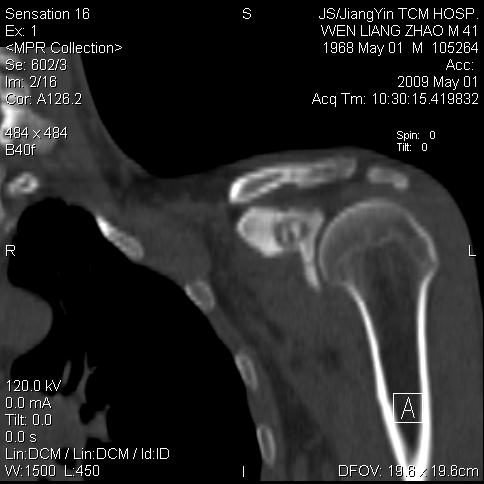

标题: CT19762:左侧喙突处压痛二年。考虑骨样骨瘤。 [打印本页]

标题: CT19762:左侧喙突处压痛二年。考虑骨样骨瘤。

左侧喙突处压痛二年。考虑骨样骨瘤。

病灶外缘膨胀明显,灶缘硬化较少,结合病史较符合骨母细胞瘤,其他亦不排除如软骨及软骨母细胞瘤等(病灶形态,成份较符合,发病部位也符合,只是年龄较大),骨样骨瘤多有较明显的自发性痛,且夜间痛明显,病史为压痛两年,不太符合.

多考虑内生性软骨瘤。年龄及发病部位及病史不支持骨样骨瘤。

支持骨样骨瘤(瘤巢小于1.5mm),骨母细胞瘤又称为巨大骨样骨瘤指瘤巢大于2cm的骨样骨瘤.

首先考虑内生软骨瘤,其次才考虑骨样骨瘤。

良性骨病(低毒感染,成软骨细胞瘤.)